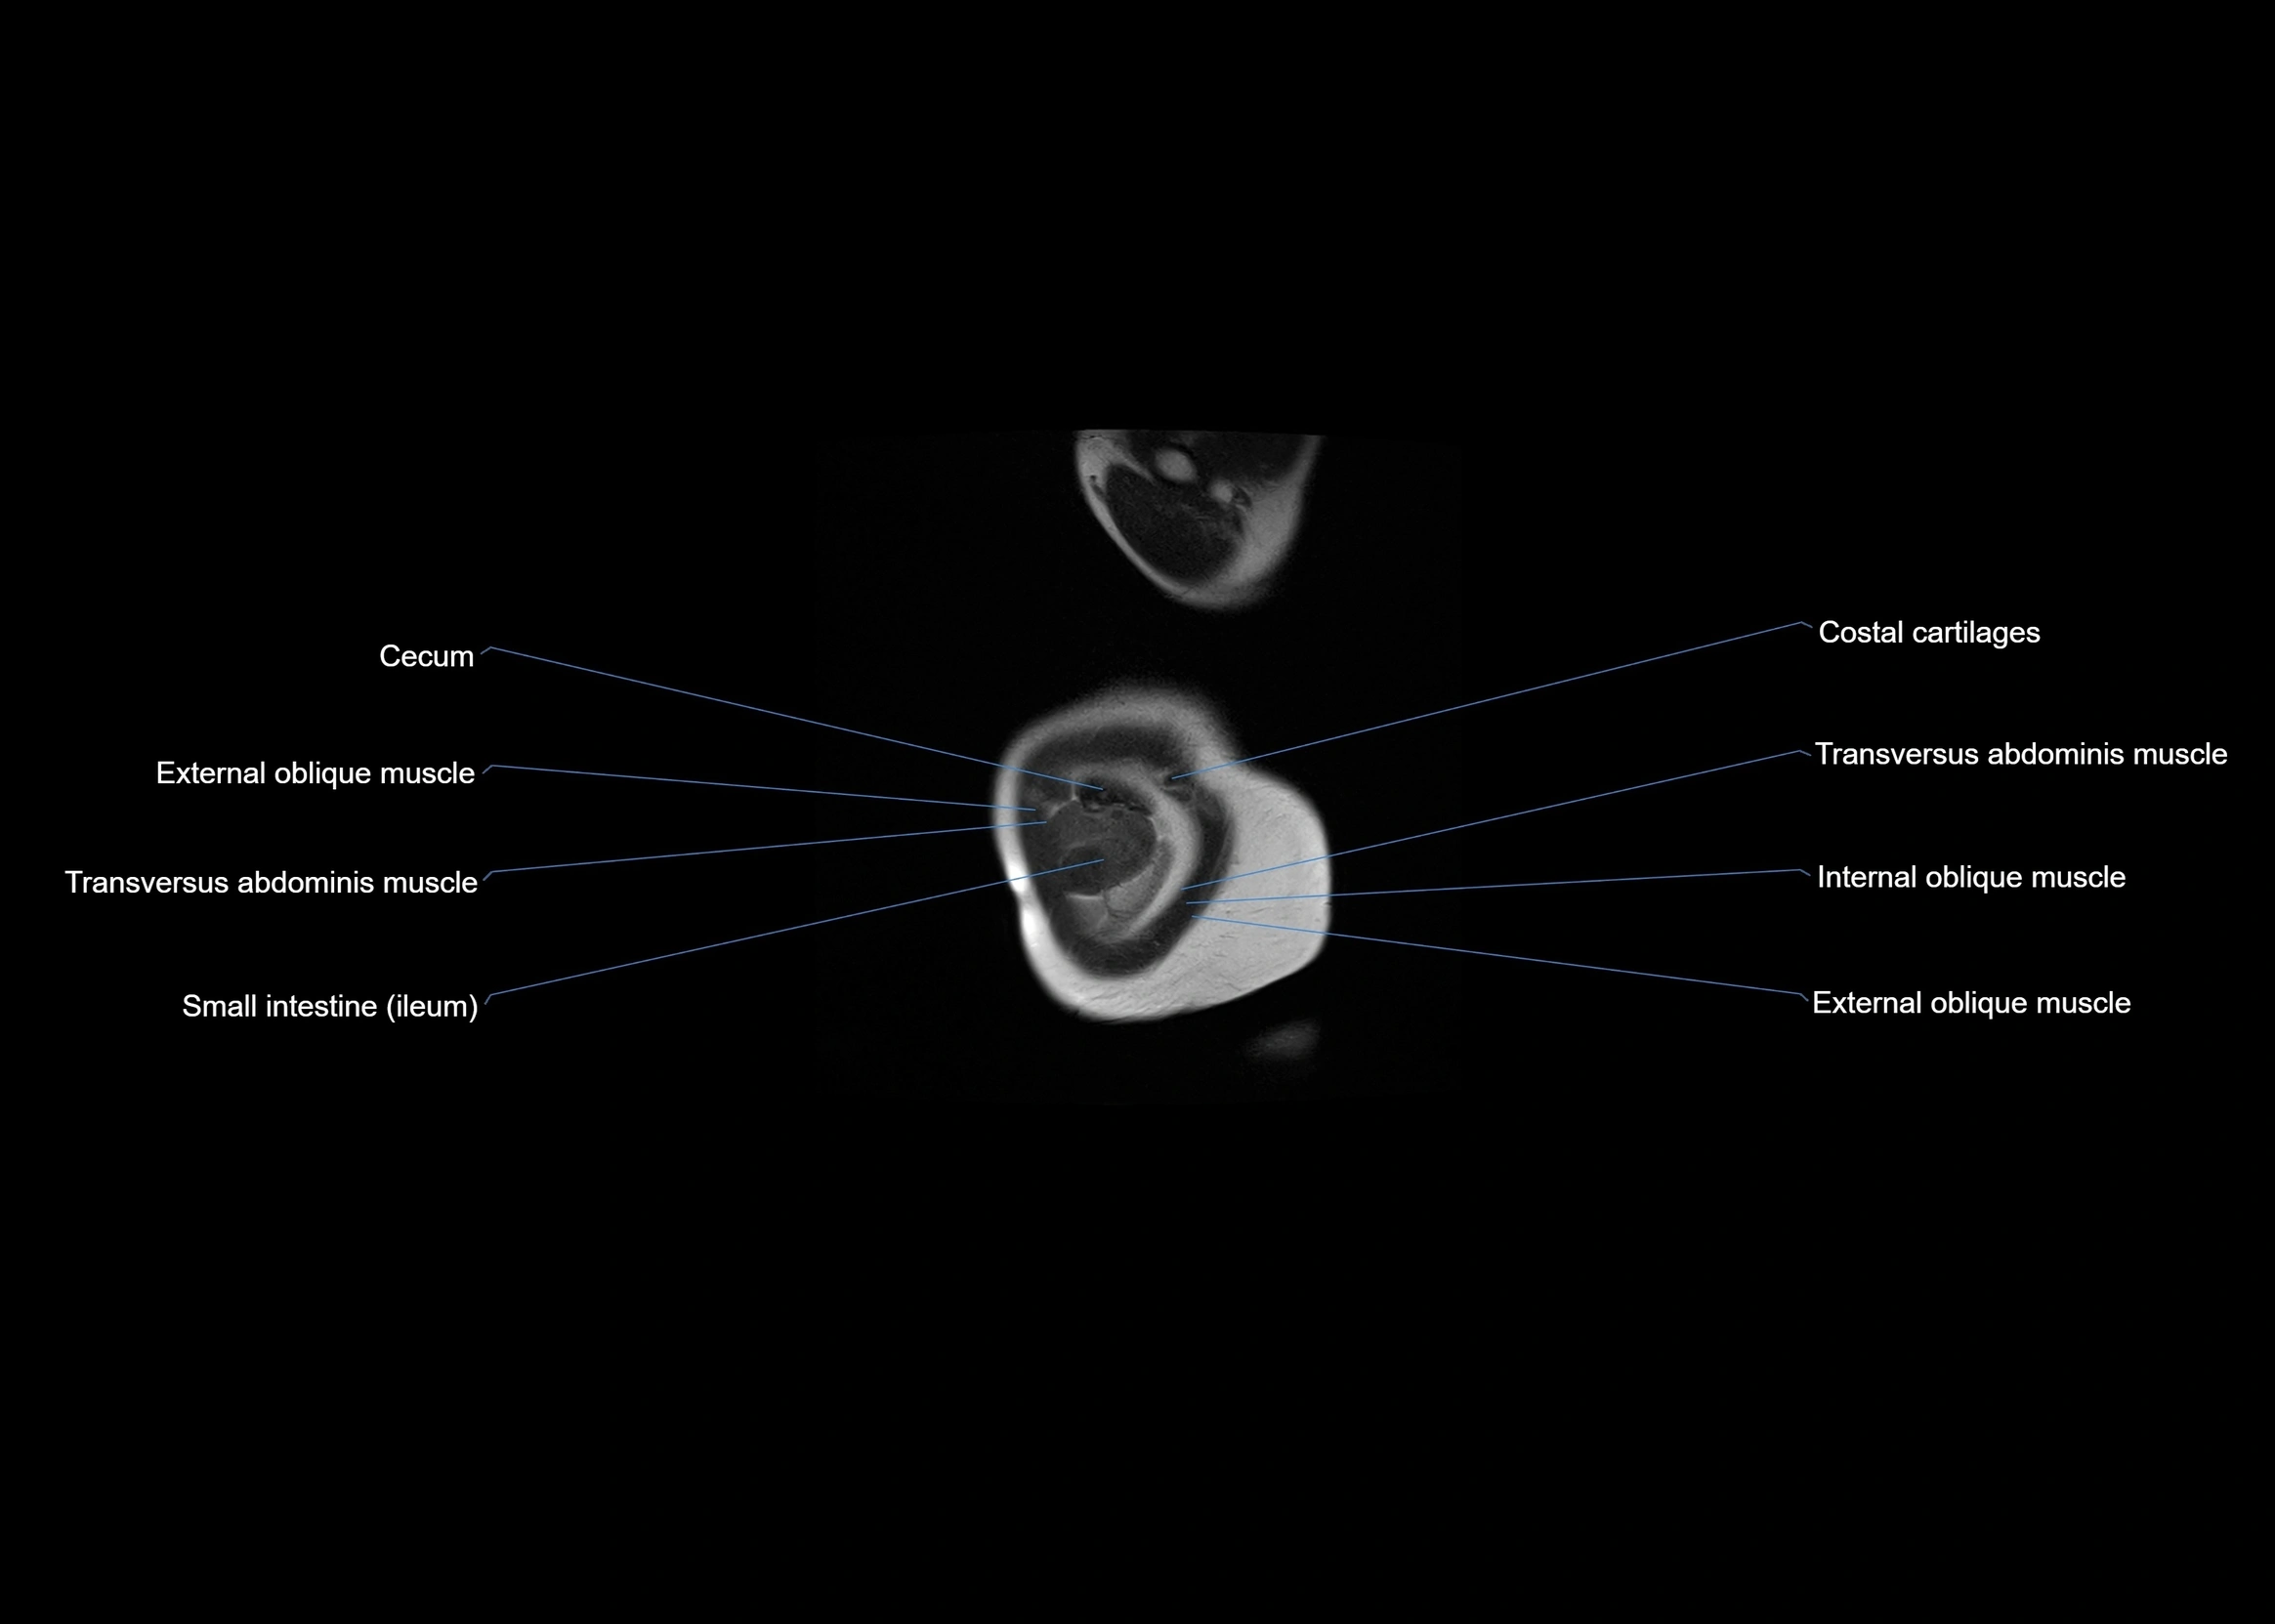

- Cecum

- External oblique muscle

- Ileum

- Internal oblique muscle

- Transversus abdominis muscle